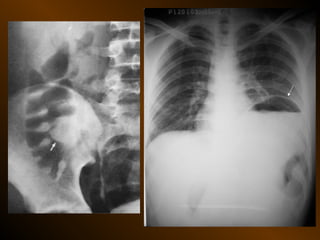

TỤ DỊCH NGOÀI PHÚC MẠC

• Khoang quanh thận

– thận, tuyến thượng thận, niệu quản

• Khoang cận thận trước

– tá tràng, tụy, đại tràng lên, đt xuống

– động mạch gan, lách

• Khoang cận thận sau

– Động mạch chủ bụng, bạch mạch

– Thân đốt sống

– Tá tràng, tụy, đường mật, đại tràng

– Ruột thừa sau manh tràng, đm gan, lách